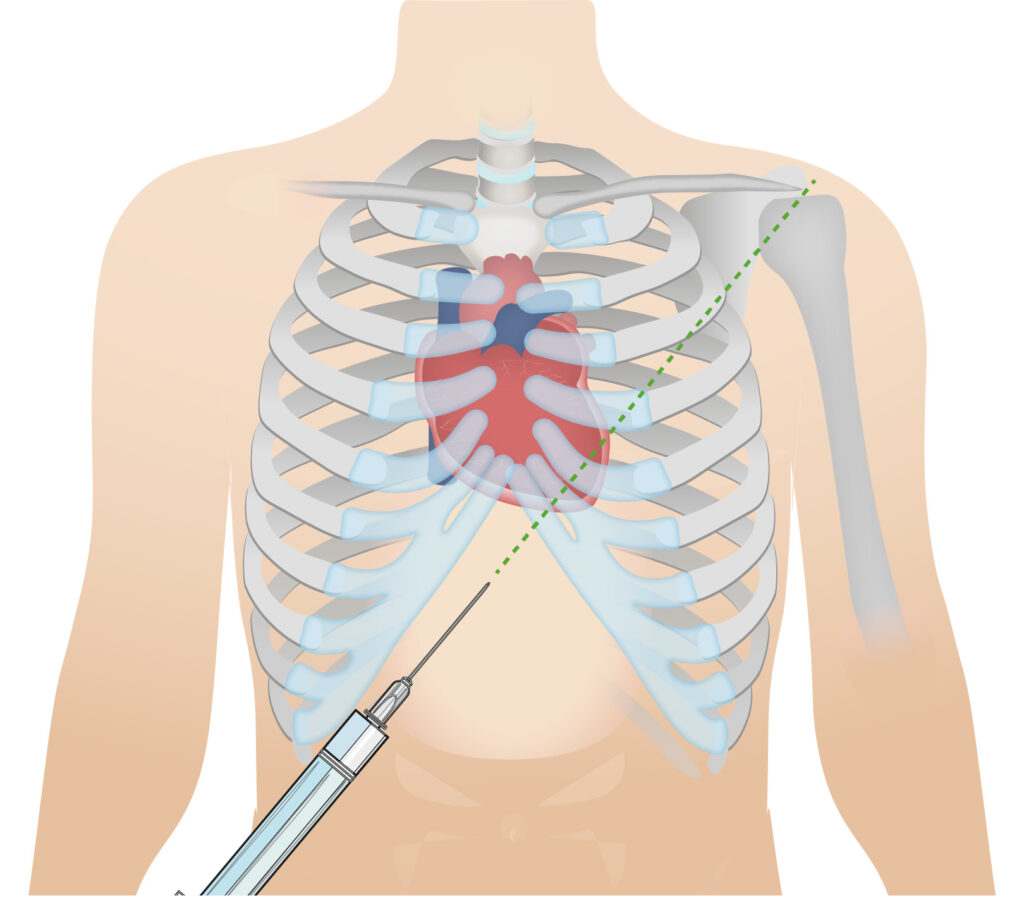

- Terapia definitiva: El tratamiento definitivo para el taponamiento pericárdico es el drenaje del líquido acumulado en el espacio pericárdico. Esto se realiza a través de un procedimiento llamado pericardiocentesis, en el cual se inserta una aguja o un tubo fino en el pericardio para drenar el líquido bajo presión. La pericardiocentesis se realiza guiada por ecocardiografía para una mayor precisión y seguridad.